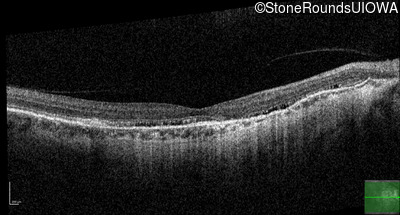

Age at visit: 58 years